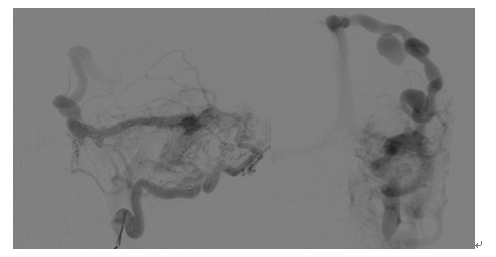

术中造影

术中介入治疗后

该病人是一名42岁的黑龙江籍男性,长期在北京打工,9月1日突发剧烈头痛、右上肢偏瘫,就诊于天坛医院急诊科,行CT检查显示颅内左顶血肿,脑水肿明显;进一步完善CTA发现左侧异常迂曲增粗的巨大静脉及位于血肿中心的巨大球球瘤,双侧头皮颞浅动脉和枕动脉异常增粗,颅底脑膜广泛供血。急诊收入脑血管三病区,考虑脑膜脑动静脉瘘,病情复杂,同时颅内出血量大,颅内血管畸形情况不明确,手术风险极高,拟进一步完善造影检查再行手术治疗,给予脱水保守治疗。入院后第三天早上8时,病人突发意识障碍加重,左侧瞳孔扩大,光反应消失,正在科室讨论病情的赵继宗院士及张东主任医师查看病人,查体后考虑病人发生脑疝,需要急诊手术干预,迅速判断病情后,赵继宗院士和张东主任认为该病人非常适合进入复合手术室进行抢救,随后张东主任团队紧急联系手术室及神经介入科,组织相关医护团队转运病人至复合手术室,以最快的速度开始抢救,经降颅压、气管插管等紧急抢救后病情暂时平稳,病人瞳孔恢复正常。神经介入科杨新建主任团队接到通知后第一时间赶到手术室,首先进行脑血管造影,明确了巨大硬脑膜动静脉瘘的诊断,后使用弹簧圈和血管栓塞剂成功封堵瘘口,明显降低了开颅手术的风险。随后张东主任团队迅速进行开颅手术,在术中B超,和电生理监测下,成功清除脑内血肿,术中发现巨大静脉球瘤为出血责任部位,予以夹闭,同时行去骨瓣减压术,解除脑疝,最终手术历时10小时,顺利结束,病人平稳转运回重症监护病房,苏醒后意识水平及神经功能明显改善。术后经过科室医护团队的精心治疗与护理,病人于9月15日出院,出院时病人神清语利,双侧肢体肌力正常,无明显神经功能障碍,生活完全自理,拟6月后回院行颅骨修补手术。